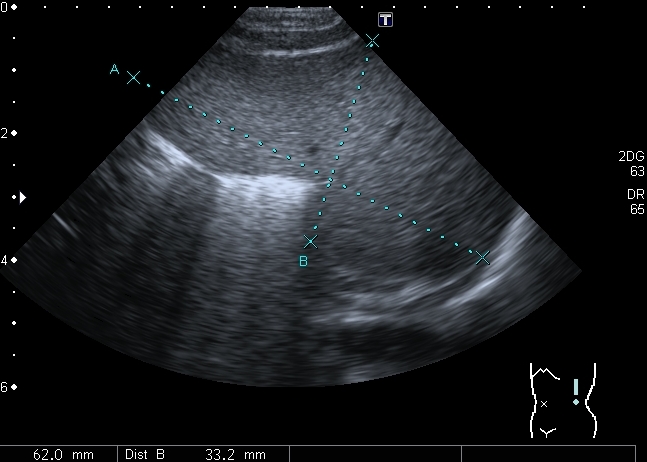

Ребёнок 1-го месяца, оперирован по поводу ВПС, транспозиции магистральных сосудов. В послеопреационном периоде сепсис. Сейчас пришли для обследования перед направлением на МРЭК

Почка Андерсона-Карра. По периферии пирамид определяются эхогенные «кольца» из-за накопления там депозитов кальция.

У детей наиболее частой причиной нефрокальциноза является первичный тубулярный ацидоз и первичная гипероксалурия.